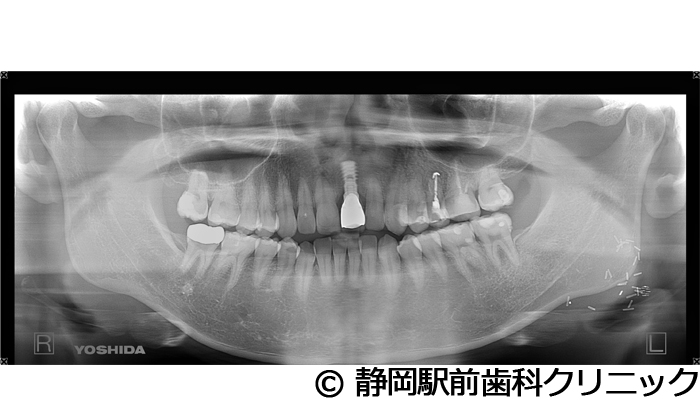

【症例2】上顎前歯単独インプラント埋入

- 治療前

- 治療後

- 治療名

- 上顎前歯単独インプラント埋入

- 費用

- 385,000円(税込)

- 期間

- 7ヵ月

治療内容

患者様の症状

上の前歯の入れ歯を使っていたが、違和感があるし、毎日手入れが大変なのでインプラント治療希望。

治療方法

術前にCTや歯型などの資料を取り、前歯のため審美性も考慮し、綿密に治療計画を立てました。その後、インプラントを埋入し、人工歯を被せて審美と咬合の回復を行いました。

治療結果

自分の歯のような見た目で、違和感もなく噛むことができてご満足いただくことができました。

※治療結果は個人差があります。

治療を行う上での注意点(リスク・副作用)

術後は、出血、腫れ、痛みなどが出る可能性があります。